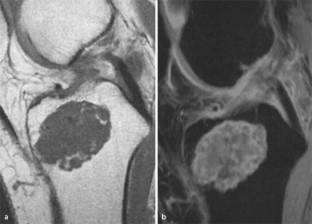

MRI morphology of bone tumors and tumor-like lesions

Für das Staging und die Charakterisierung von Knochentumoren und tumorähnlichen Läsionen ist in der Magnetresonanztomographie (MRT) der Einsatz von Spinechosequenzen erforderlich. Die MRT hat nur einen geringen Stellenwert in der Bestimmung der Dignität. Obwohl viele Knochentumoren und tumorähnliche Läsionen eine vergleichbare Morphologie in dieser bildgebenden Modalität aufweisen, können einige Tumorentitäten mittels MRT recht zuverlässig diagnostiziert werden. Hierzu zählen Knorpeltumoren, die solitäre und aneurysmatische Knochenzyste, der Riesenzelltumor, fetthaltige Läsionen und bis zu einem gewissen Grad auch das Osteoidosteom und das Osteoblastom. Es werden praktische Tipps gegeben, wann bei Tumorverdacht die MRT eingesetzt werden sollte, wie bei einem zufällig bei einer MRT gefundenen Tumor die Untersuchung modifiziert werden sollte und welcher Tumor vorliegen könnte.

Spin-echo sequences are mandatory at MRI for staging and characterization of bone tumors and tumor-like lesions. MRI is of minor value in the estimation of the malignant potential of an osseous lesion. Although many bone tumors and tumor-like lesions present similar morphology at MRI, some entities can be diagnosed with good reliability. These include chondrogenic tumors, solitary and aneurysmal bone cysts, giant cell tumors, lesions containing fatty tissue and, to a certain extent, osteoid-osteomas and osteoblastomas. Practical advice is given regarding when to perform a MRI study in cases of tumor suspicion. Further advices are given for cases a tumor is found incidentally at a MRI study, how to modify the study and which kind of tumor may be present.